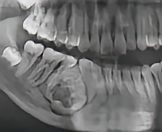

非均质性成牙骨质细胞瘤